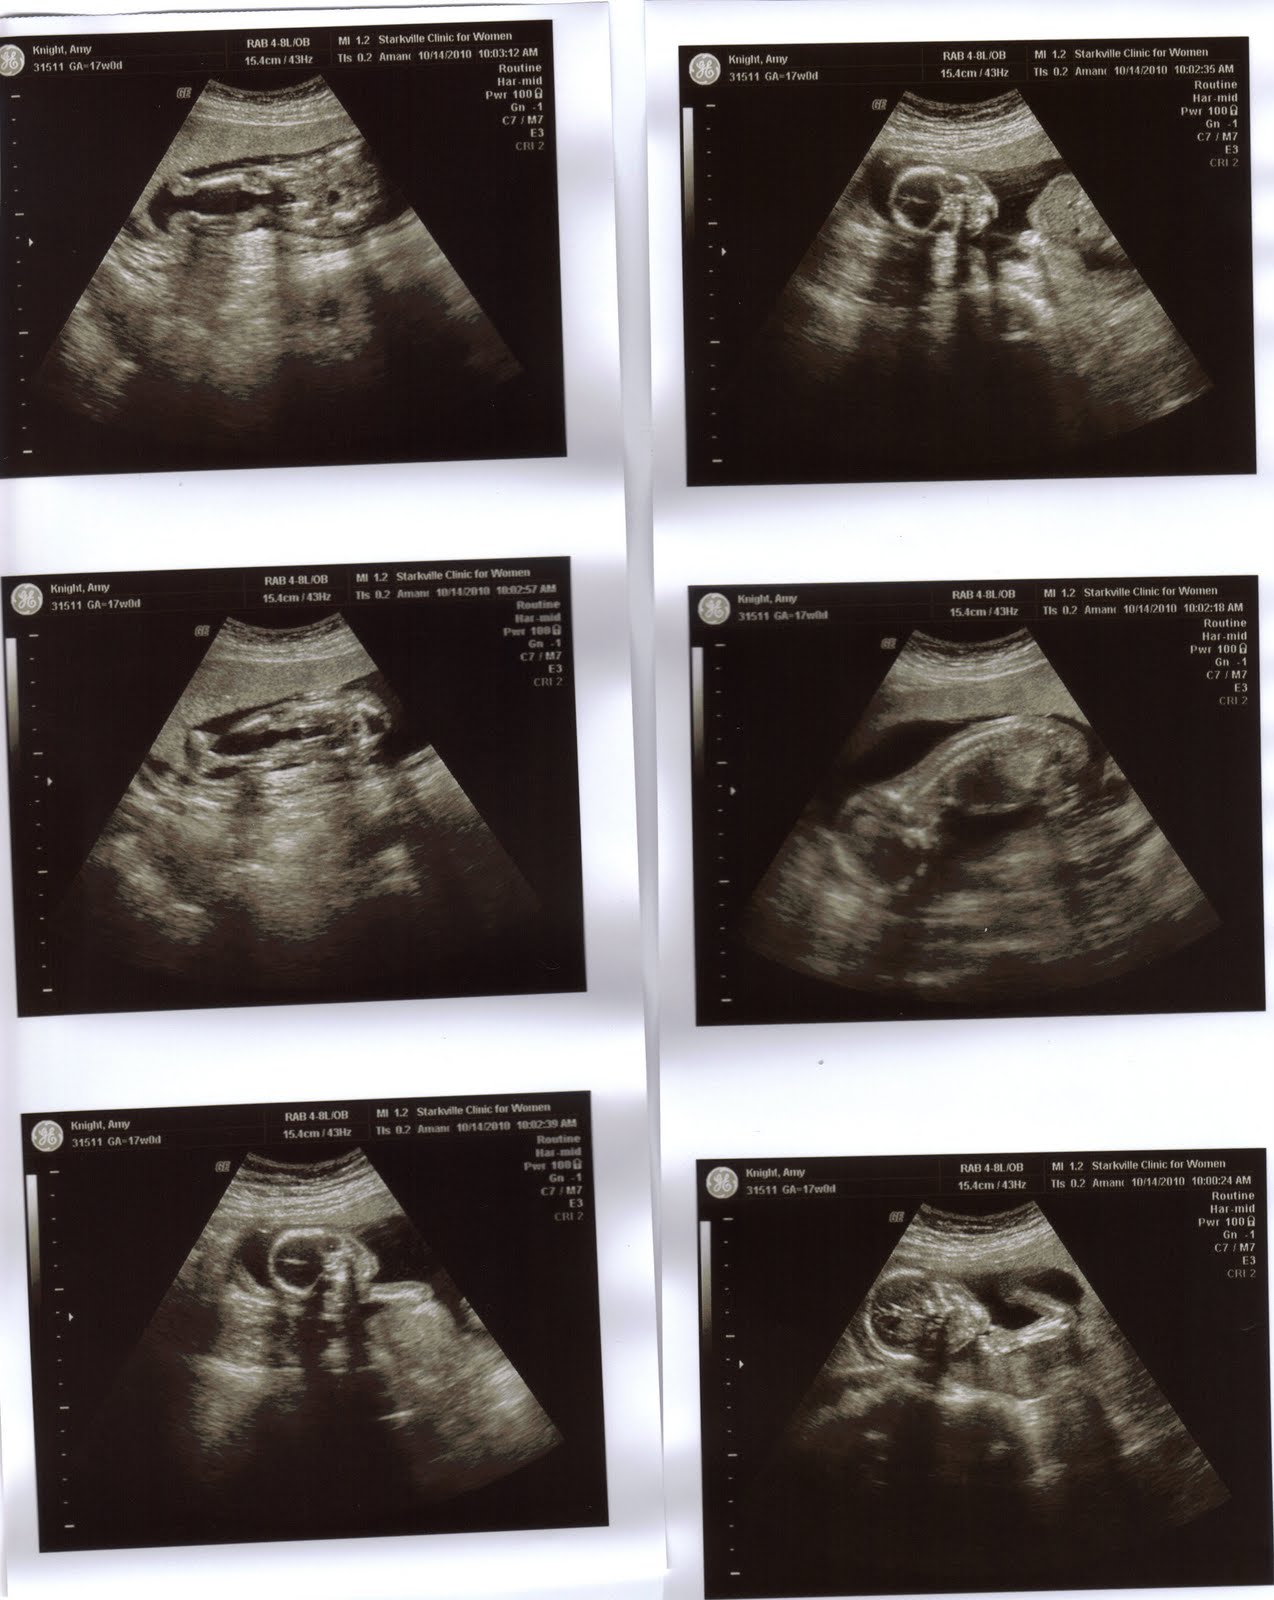

Well, my wife is 17 weeks pregnant, and yesterday we found out that we are having a boy!! We are very excited (me especially), and the best news was that the baby is developing normally. I've attached some pictures, you can really see the development of his spine, legs, arms, and skull in these pictures. It is truly amazing that even though he is a little less than a foot in length and weighs about half a pound you can see all these body structures. We discussed prenatal development in class a few weeks ago and it is really cool to be able to see this in your own child. By this point, his brain configuration is nearly complete, his heart muscle is developed, and he has begun motor activity. The skeleton, which begins as a cartilage model, is beginning to ossify. Many other changes will occur during the next five months until we welcome him into the world.